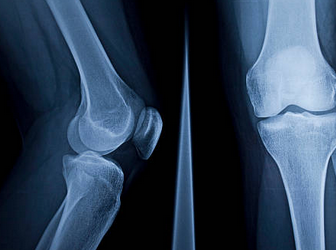

무릎 연골 찢어짐의 증상으로는 무릎 통증, 부기, 딸깍거리는 소리, 무릎의 움직임 제한 등이 있습니다. 만약 이러한 증상이 지속되거나 심해진다면 병원에서 정밀 검사를 받아야 합니다. 일반적으로 X-레이와 MRI 검사를 통해 무릎 연골 찢어짐의 정도와 위치를 확인할 수 있습니다.

무릎 연골 찢어짐의 진단은 X-레이나 MRI 검사를 통해 할 수 있습니다. X-레이는 뼈의 손상을 확인할 수 있고, MRI는 연골과 인대 등의 부드러운 조직의 손상을 확인할 수 있습니다. MRI 검사 비용은 보험 적용 여부에 따라 다르지만, 대략 35만 원에서 50만 원 정도입니다 .